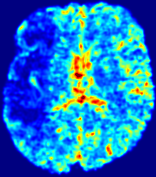

Figure 6: Predicted concentration time series for the same patient shown in Fig. 4, where (i)-(vi) correspond to slices #1-6 respectively. Each grouped row displays (a) the measured concentration image sequences and (b) the predicted concentrations at corresponding time points.

3.2 Predicted CA Concentration

To better illustrate the prediction accuracy, and therefore the estimation accuracy of 𝐕𝐕{\bf V} and D𝐷{D}, of PIANO, we provide the corresponding predicted time-series of CA concentration images in Fig. 5 and Fig. 6 for the same patients in Fig. 3 and Fig. 4, respectively. We see that PIANO is capable of predicting the CA concentration given their initial state, indicating its ability to successfully capture 𝐕𝐕{\bf V} and D𝐷{D}. Note that although the concentration values for these two patients differ considerably, caused by the different total volume of injected CA, PIANO is still able to provide plausible estimates.